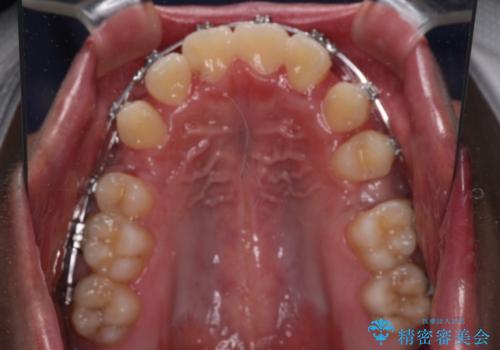

- 矯正装置

- メタルブラケット

- 前歯のデコボコと口元の突出感を気にして来院された患者様です。

上下前歯がくちばしのように突出していたため、上下左右の第一小臼歯4本を抜歯し、ワイヤー装置にて矯正治療を行うこととしました。

左上は第二小臼歯が90度捻れており、状態が良くない歯であったため、左のみ第二小臼歯を抜歯することとしました。

第二小臼歯抜歯により治療期間が長くなることを了承いただき、治療を開始しました。